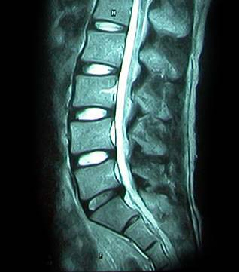

HLD on L-spine, Lt. L5 & S1 Radiculopathy

64세 여자환자는 2개월 전부터 요통과 다리 바깥쪽과 발등, 종아리 뒤쪽으로 저린 감각이 심해져서 개인병원에 들러 평가 및 물리치료를 받았으나 별다른 호전이 없고, 1주일 전부터는 허리를 숙이거나 물건을 들 때, 오래 걸을 때 통증이 더 심해져서 본원을 방문하였다. 12년전 집안일을 심하게 하고 난 후부터 간헐적인 요통을 발생하였으며, 별다른 치료 없이 지냈으며, 4년전 무거운 물건 들고 난 후 심하게 요통과 둔부의 통증까지 발생하여 MRI 촬영상 L1-2, L3-4-5, L5-S1 HNP와 Lt. L4 & both L5 nerve compression, Lt. S1 nerve compression 진단받고 Epidural steroid injection을 받고 통증 경감되었고, 간헐적으로 통증이 발생하였으나 별다른 치료 없이 헬스클럽에서 지속적인 운동으로 관리하였다.

• 척추 방사선 사진2